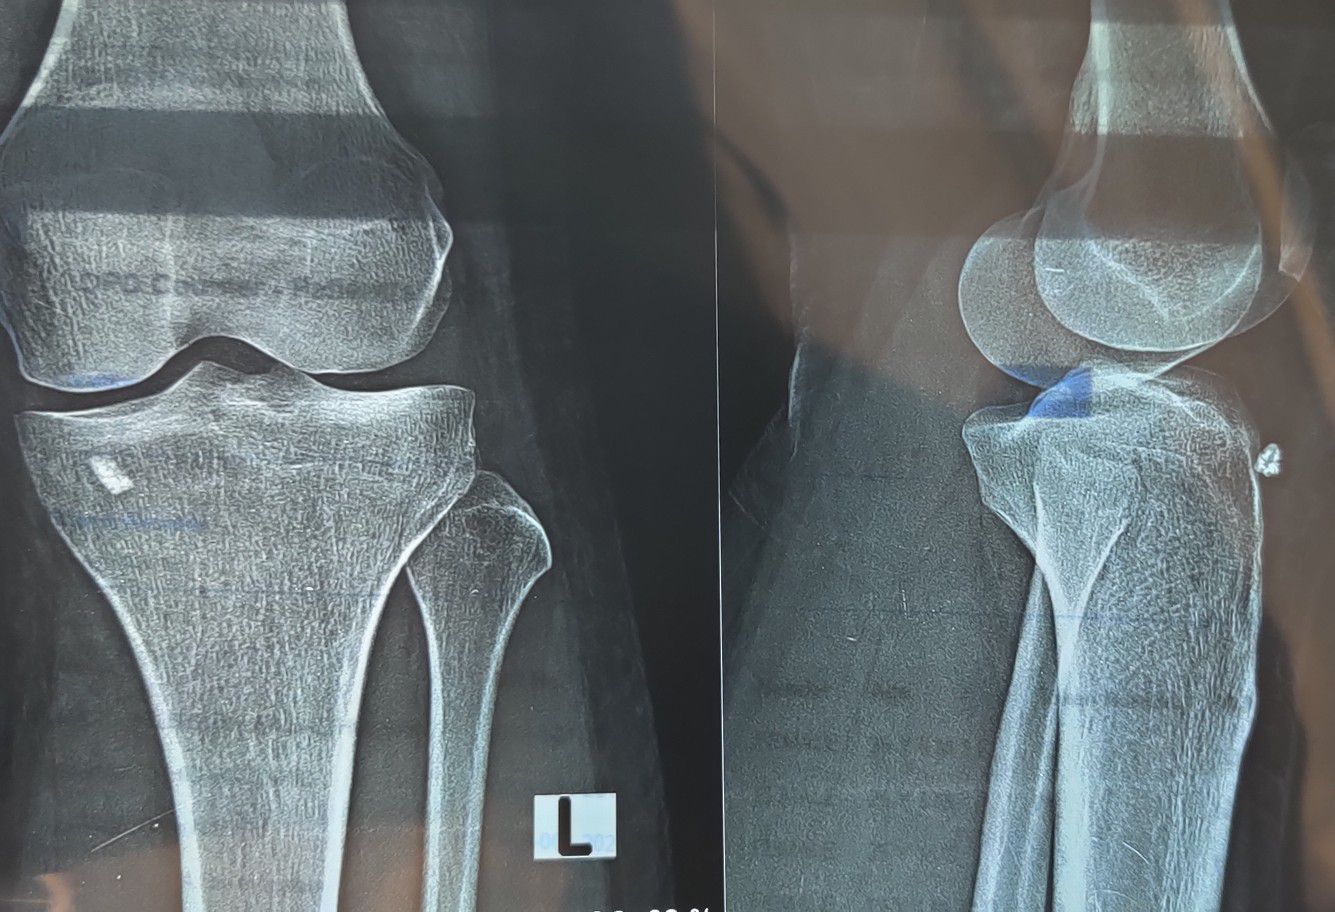

Foreign Body

Xray

Orthopaedics